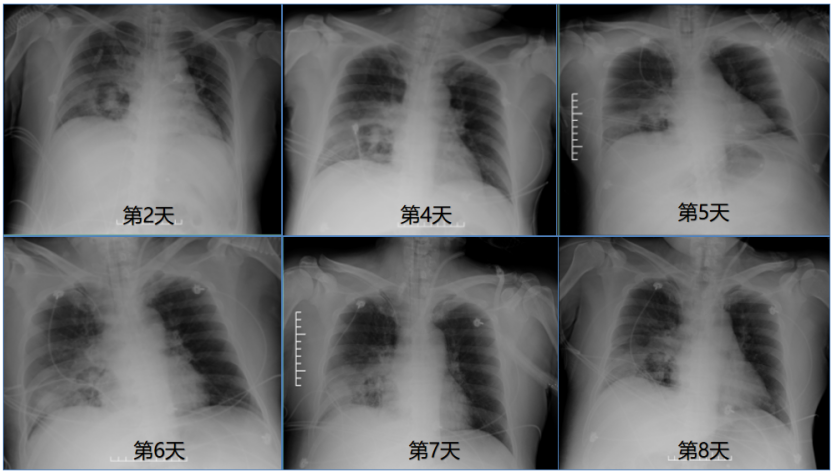

相关辅助检查

第2~8天随访胸部X线片示:肺部感染病灶范围稍减小

(图3)

图片

图3  患者胸部X线片